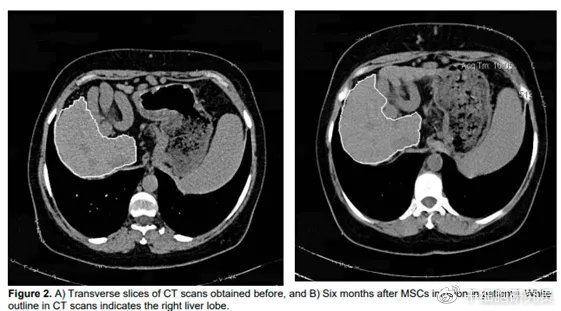

在一项一期临床试验中[6],四名失代偿期肝硬化患者接受外周静脉输注自体间充质干细胞。这些患者在随访期间没有发生副作用,有一半患者的Mayo终末期肝病评分有所改善。此外,在随访结束时,所有四名患者的生活质量都有所改善。